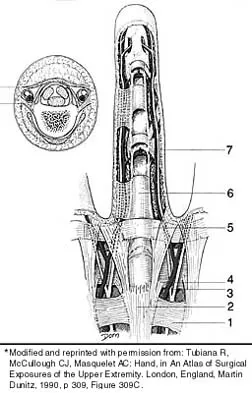

Which of the following anatomic structures is labeled 6 in Figure 27?

Explanation